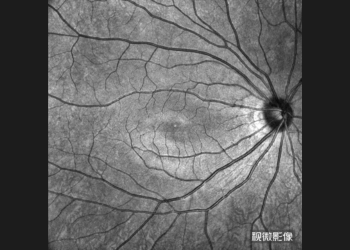

OCTA montage captured with VG-200C